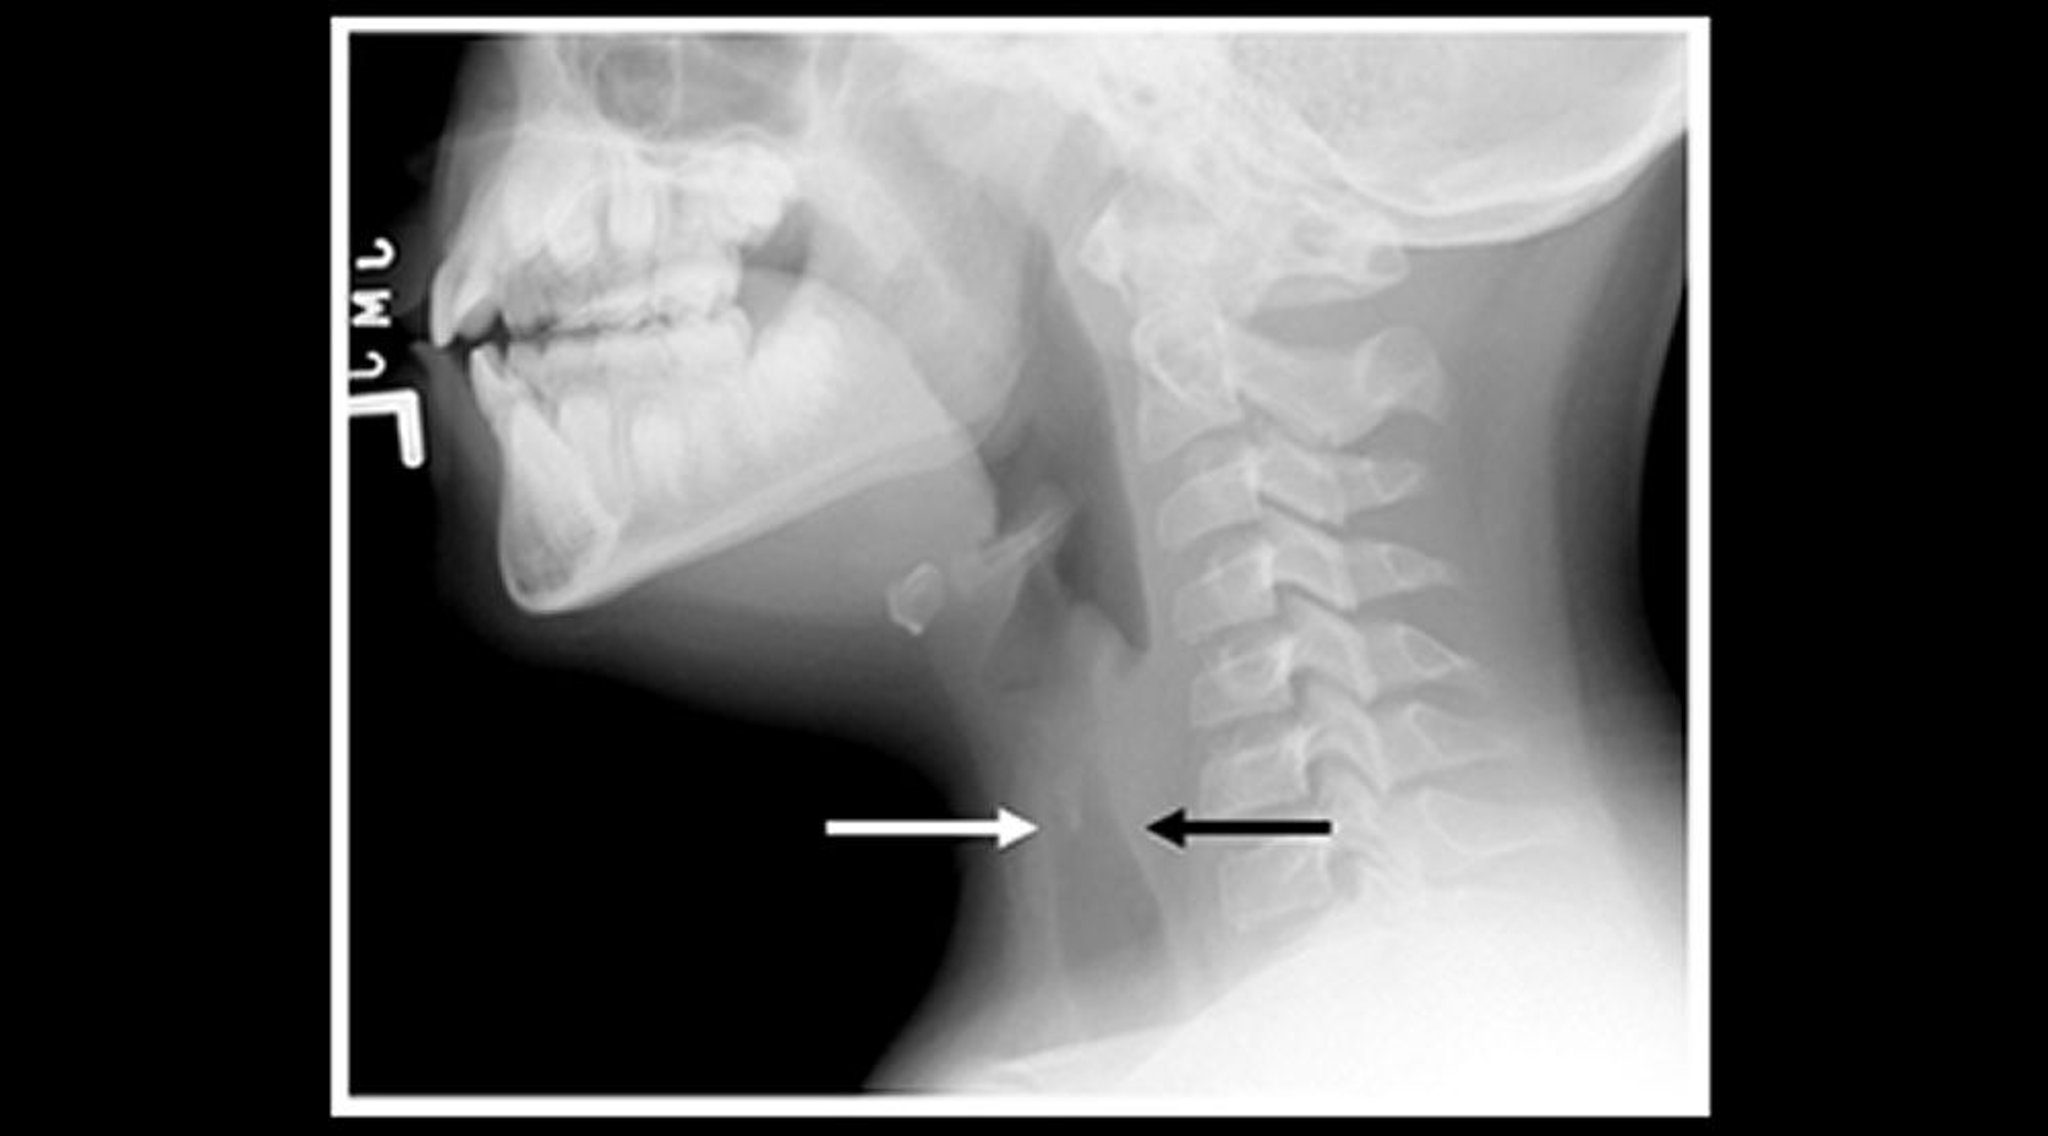

Radiographie d'un enfant atteint de laryngite striduleuse (vue sagittale)

Les radiographies du cou des tissus mous d'un enfant qui a une laryngite striduleuse montrent un rétrécissement de l'ombre trachéale sous-glottique (flèches) et une dilatation des espaces aériens pharyngés.

Image courtoisie de John McBride, MD.